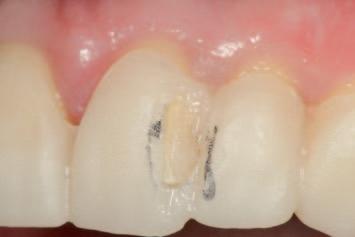

n The tooth reduction guide is tried into the mouth to confirm complete seating and to assess the extent of the anticipated interferences clinically (Figure 2).

FIGURE 2: Initial seating of the preparation guide on the dentition allows the clinician to visualise the intended outcome of this treatment step.

A C B

The external contours of the guide correspond to the planned final contours of the definitive restoration. Regions of the underlying dentition that protrude from the guide windows represent interferences, which must be selectively reduced to achieve the intended outcome. Importantly, this will act as a preliminary reduction, as an initial step prior to conventional tooth preparations for crowns.